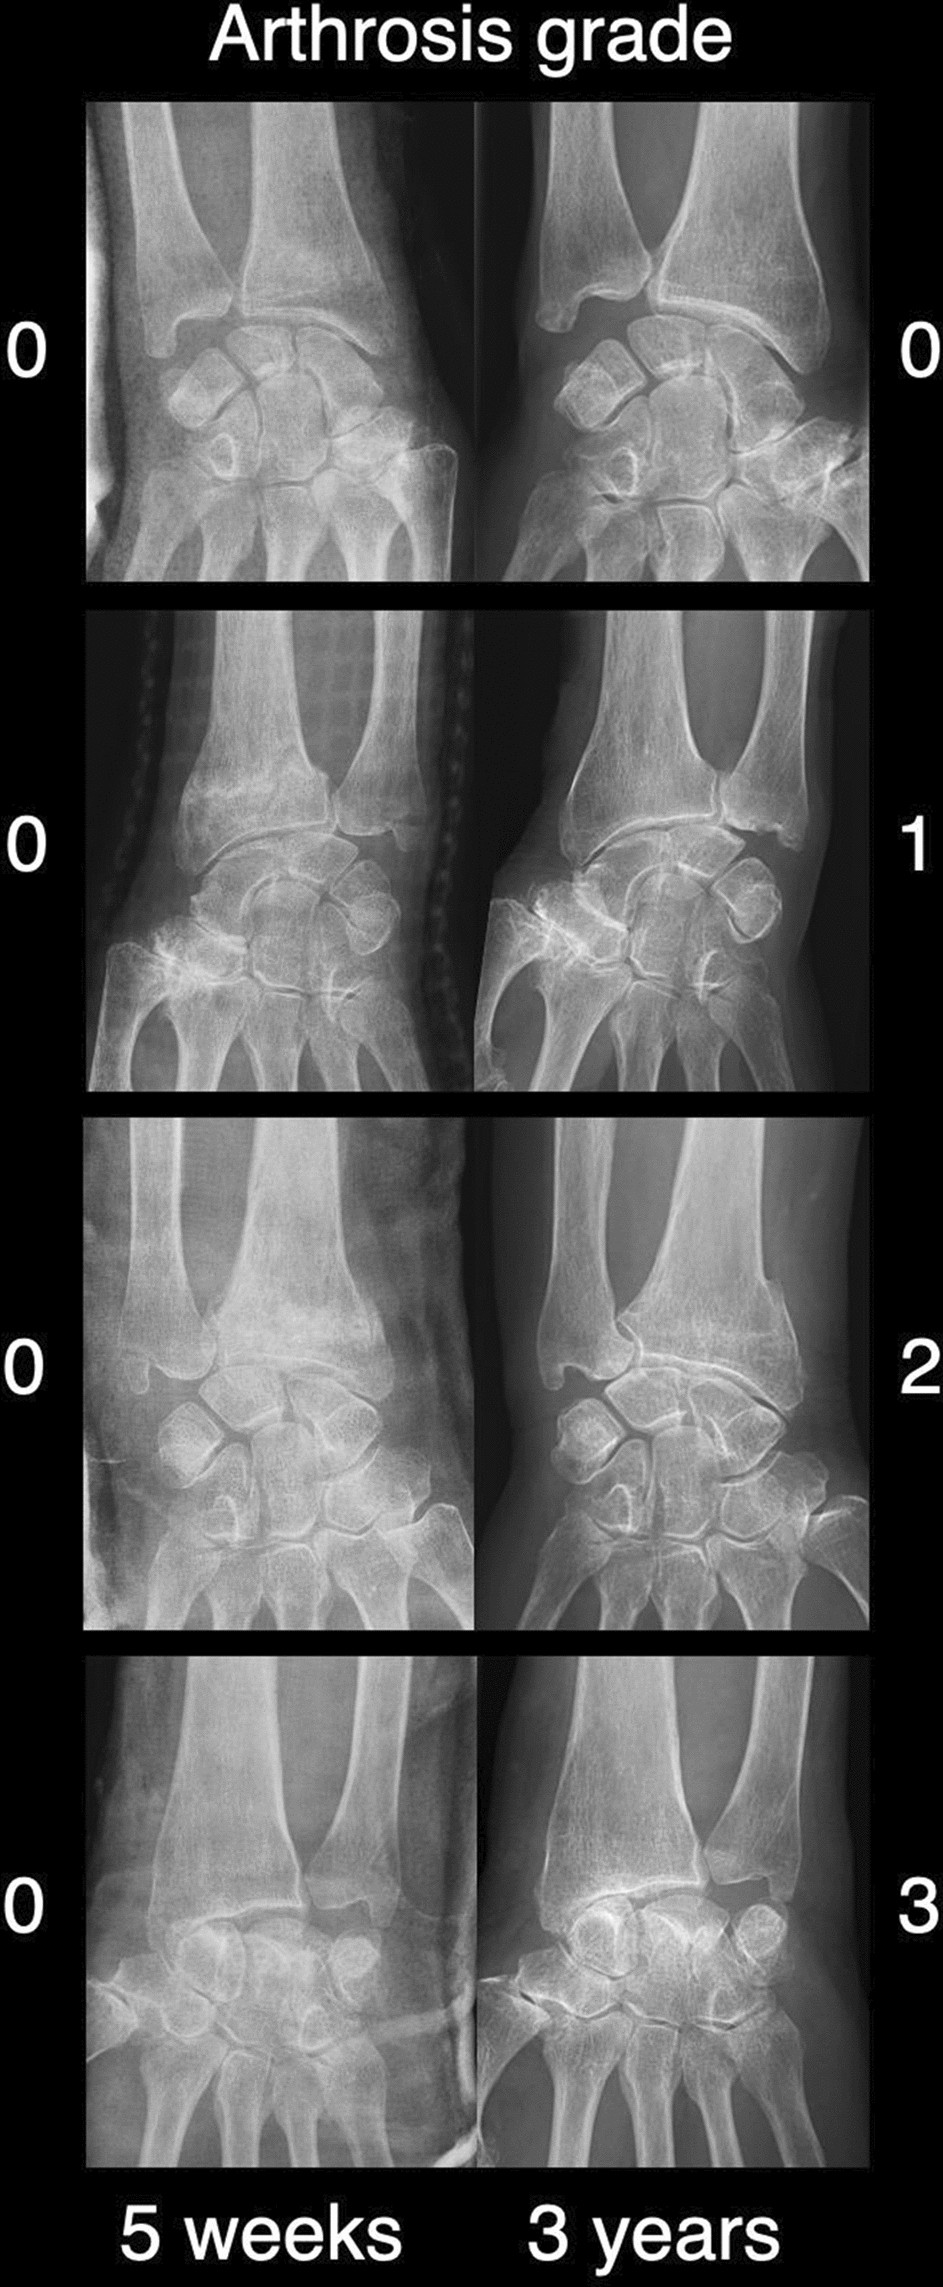

Figure 2

Examples of assessed anteroposterior radiographs with posttraumatic arthritis (PA) grades 0, 1, 2, and 3 after 5 weeks and a mean of 3.3 years after the injury.